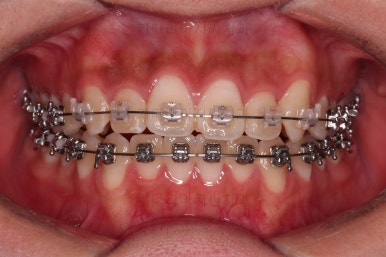

장치를 처음 부착했고요.

이번 환자분이 선택한 장치는 윗니는 세라믹 자가결찰인 엠파워 클리어, 아래는 메탈 자가결찰인 엠파워 메탈입니다. 둘 다 같은 회사의 같은 세팅의 장치이므로 혼용이 가능하죠. 대신 비용은 좀 더 줄일 수 있습니다.

초기 6개월 이내에 어느 정도 치열이 가지런해 졌네요.

중간평가 들어갑니다.

앞니가 많이 뻗쳤나요?

그렇지 않죠.

대신 처음에는 삐뚤어서 가려져 있던 부정교합이 드러나면서 최소한 윗니는 교합을 위해 후방이동이 필요한 상황이긴 했습니다.